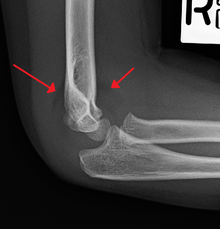

An elbow X-ray showing a displaced supracondylar fracture in a young child | |

Diagnosis is usually by x-ray. The fracture can however be difficult to identify and often a joint effusion is used to increase one's suspicion of the presence of a fracture. The existence of an effusion can be determined by the presence of the sail sign.

Upon examination the doctor will evaluate the arm for signs of damage to the nerves and blood vessels; they will look for swelling and deformity. This will allow the doctor to determine a likely diagnosis. Damage to the elbow is a common injury in children; injuries to blood supply of the arm may necessitate early surgical intervention.[4] Most of the supracondylar fractures are minor and require a period of rest, analgesia and compression prior to graduated formal rehabilitation.[5] In the event of a more severe injury, the fracture will be visible on an x-ray. It is important in diagnosis to understand the dynamics of an x-ray because growth plate fractures may not show up like normal broken bones. It is a good idea to compare the x-ray of the injured elbow to the opposing side for analysis.[4] If rest does not cause the fracture to heal then the child must be referred to a specialist for assessment of the injury.[5]